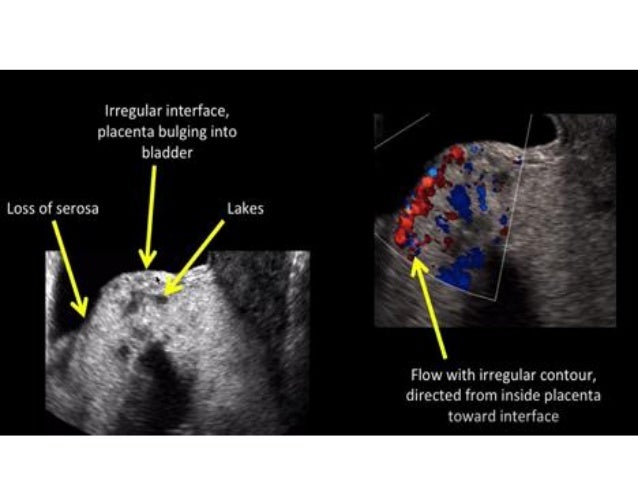

#Retained placental fragments full#

#Retained placental fragments code#